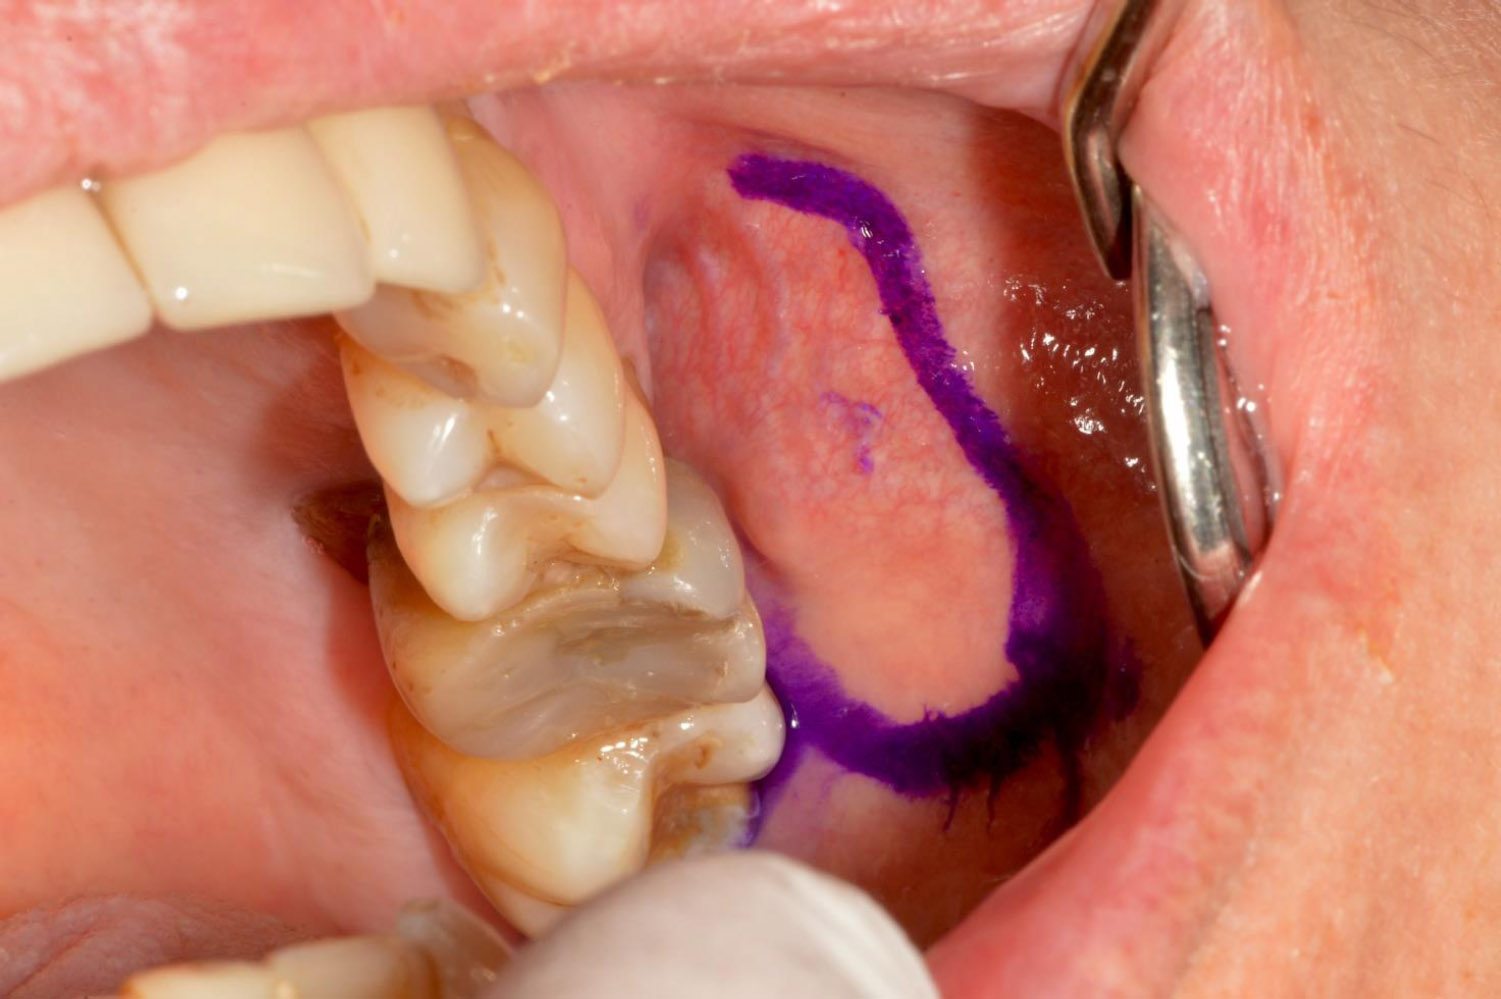

In agreement with the patient, a surgical drainage was performed. After outlining the area of the collection with a dermographic pencil (Fig. 4), a small incision (3 mm) was made in the mucosa anterior to the Stensen duct, and an 18-gauge needle was inserted. Compression of the cheek released a brownish liquid, which was aspirated (Fig. 5) and sent for microbiological analysis. Single interrupted resorbable stitches were applied [25]. Ten days later, due to the persistence of mild swelling, a second drainage was performed.

The area of the collection was identified through palpation of the cheek and carefully marked using a dermographic pencil for precise localization.